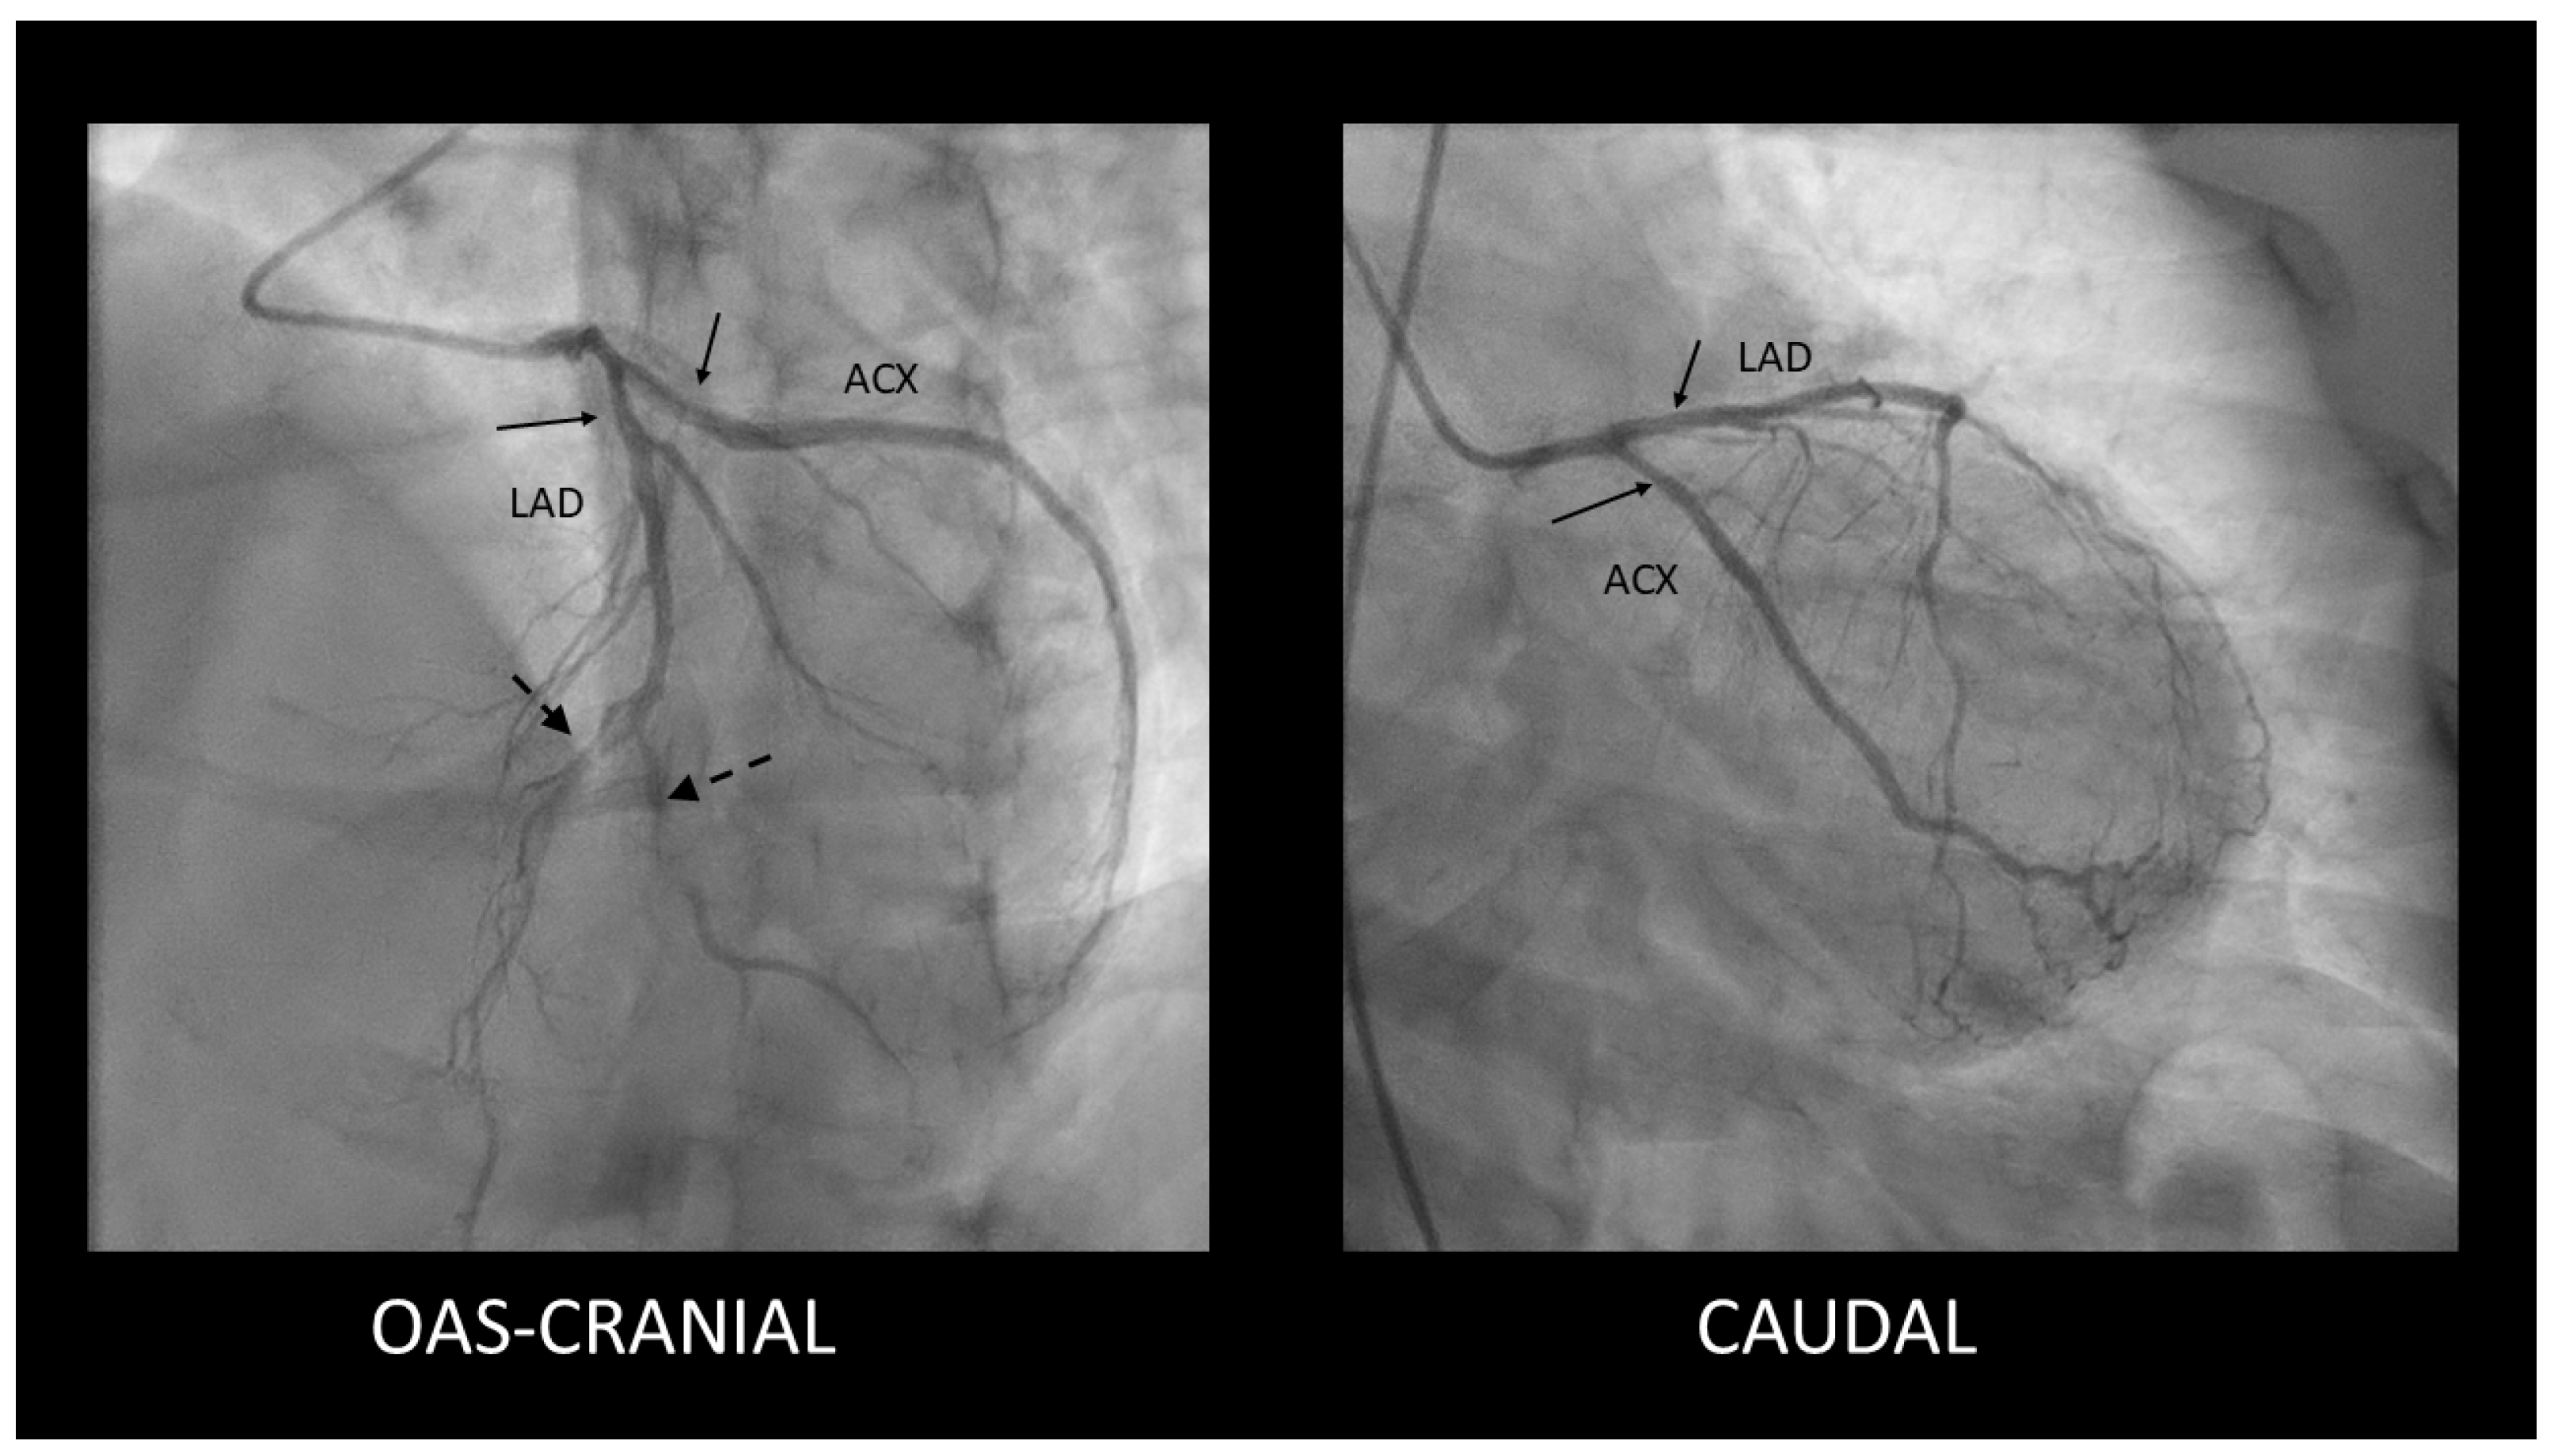

Spontaneous Coronary Artery Dissection Involving the Left Main with Extension to Left Anterior Descending Artery and Left Circumflex Artery: Diagnostic and Management Challenges

Rusali, C.A.; Cojocaru, L.; Lupu, I.C.; Uzea, C.-D.; Rusali, M.L. Spontaneous Coronary Artery Dissection Involving the Left Main with Extension to Left Anterior Descending Artery and Left Circumflex Artery: Diagnostic and Management Challenges. Diagnostics 2025, 15, 61. https://doi.org/10.3390/diagnostics15010061